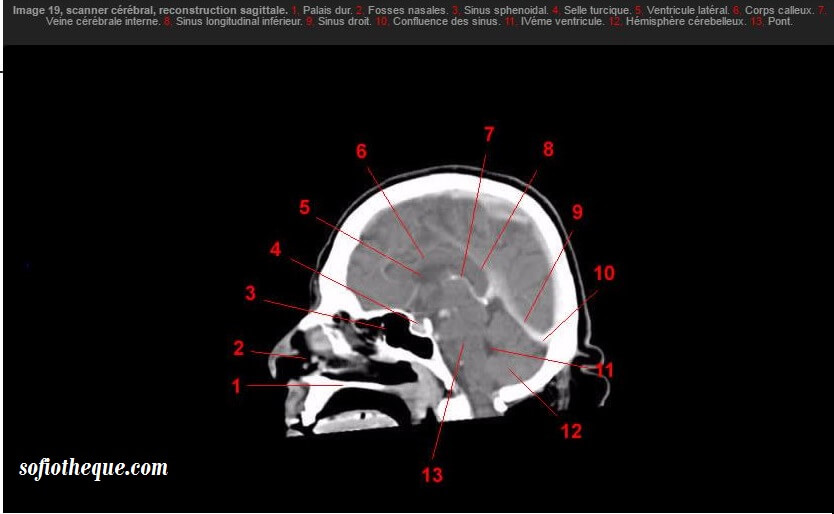

Le scanner montre un hématome sousdural frontopariétal droit subaigu (flèches rouges) Sur un scanner non injecté, le sang frais est hyperdense alors que celui plus ancien est hypodense Mais pendant un certain laps de temps le sang est d'aspect isodense comme le parenchyme cérébral, et c'est le cas sur cette image. Scanners montrant la cartographie fonctionnelle du cerveau pour trois types d’activité mentale (émotion, récompense, exécution d’une tâche) sur deux jours différents. Scanner translation in French English Reverso dictionary, see also 'scander',savonner',scandale',scansion', examples, definition, conjugation.

Scanner Du Cerveau Et De La Face Atlas Interactif D Anatomie

Atlas Anatomie Scanner Du Cerveau

Atlas Anatomie Scanner Tomodensitometrie Du Cerveau Sofiotheque